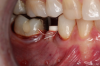

Fig 23. 12 weeks postoperatively.

Figure 23

Figure 23 showed an example of gingival soft tissue creeping occlusally and over the lingual gingival margin of the one-piece ceramic dental implant. This supragingival migration was caused by the exceptional biocompatibility due to the acid-etched surface of the implant, a one-piece implant that prevents bacterial colonization that one may find with two-piece metal-implant systems.